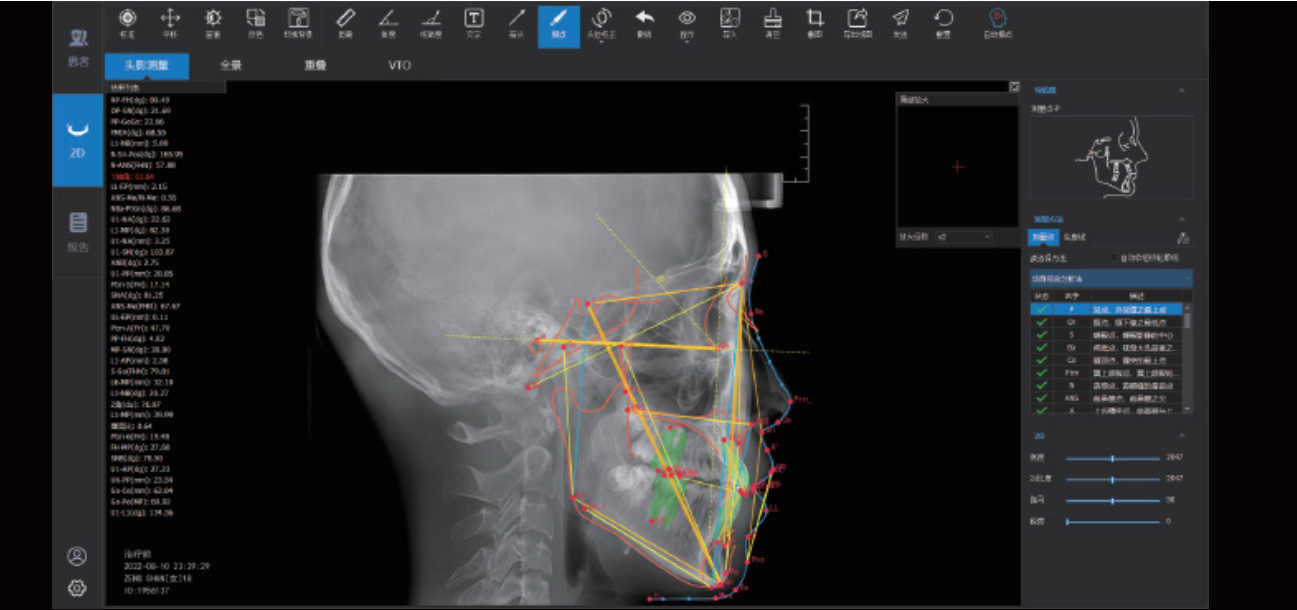

IA + Ceph Measurement(Optional)

The neural network is trained by mega data, which automatically identifies orthodontic anatomical landmark points, draws anatomical structures and outputs measurement reports according to the selected measurement methods.